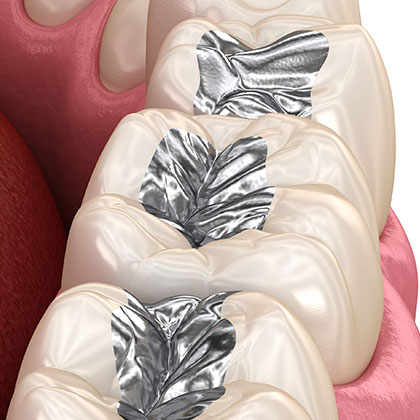

お口にこんな金属が

入っている可能があります

金銀パラジウム合金

被せ物に使われます。天然の歯より硬く、噛み合わせの衝撃が蓄積されることで、首や肩のこり、腰痛、頭痛など、全身の不調を引き起こす可能性があります。